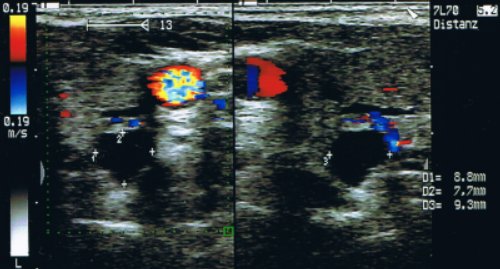

Zur Beurteilung der Morphologie wird primär die Ultraschall-Untersuchung eingesetzt. Zur genaueren Abklärung sind die Computertomographie und die Magnetresonanztomographie vorbehalten. Für die exakte Lokalisation der Nebenschilddrüsen und deren Entartungen kommt eine Tc99m-Sestamibi-Szintigrafie zum Einsatz.